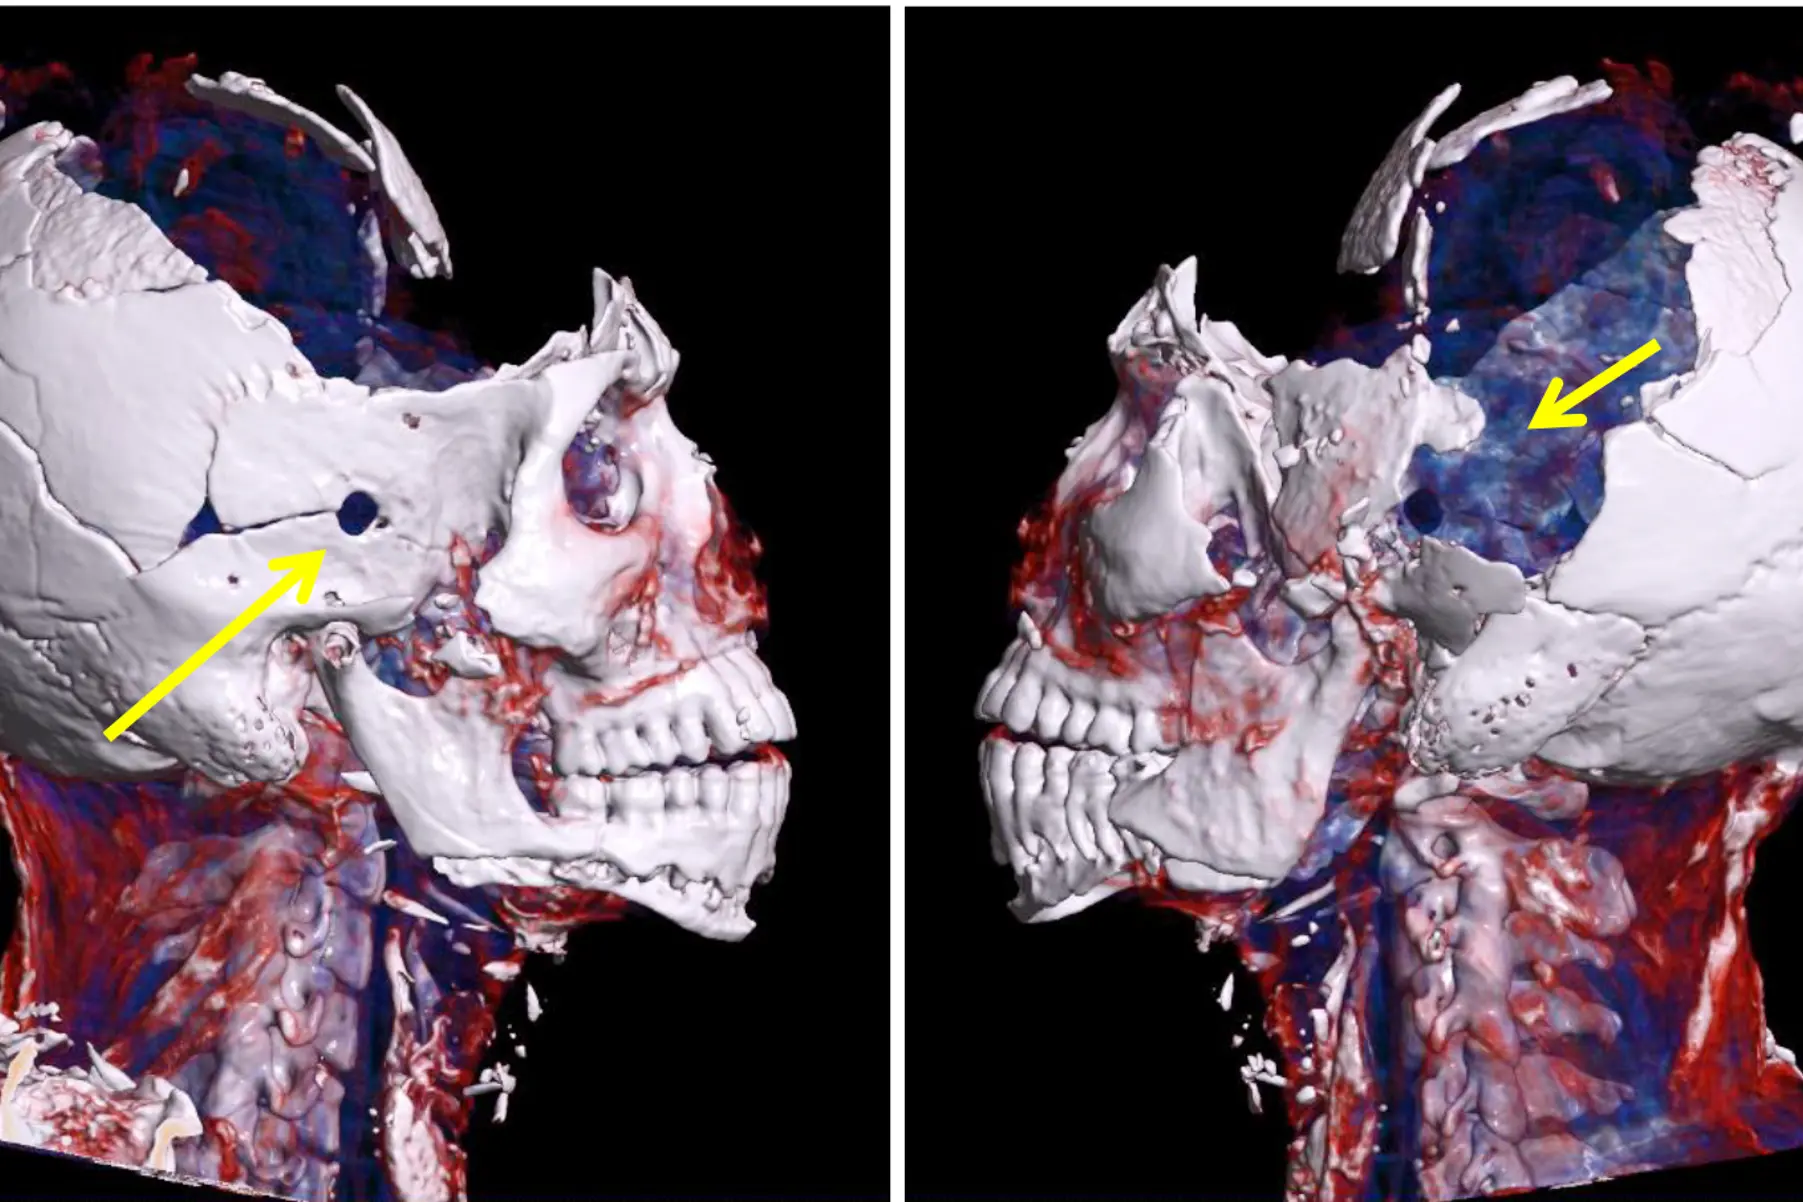

Fig 2. 3D CT-bilde som viser bruddlinjer i overkjeven og i neseroten (piler).

I Avdeling for rettsmedisinske fag ved Oslo universitetssykehus blir alle avdøde rutinemessig skannet med vår egen CT-maskin før ordinær obduksjon. I tillegg til å gi oss viktig informasjon i forkant av en ordinær obduksjon, sikrer CT-bilder objektiv dokumentasjon som vi kan bruke i rettsaker. Vi kan påvise brudd i ansiktet uten å måtte gjøre estetisk skjemmende undersøkelser, som vanskeliggjør syning av den avdøde etter obduksjonen. Generelt får vi også bedre oversikt i saker med stort skadeomfang. Undersøkelsene gir oss også mulighet til å etterprøve obduksjonsfunnene i ettertid for eksempel i forbindelse kvalitetsforbedring og forskning.